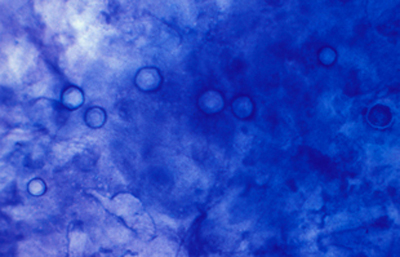

Blanco de Calcofluor

El uso del fluorocromo Blanco de Calcofluor no es excluyente de otras coloraciones, pues al ser en base acuosa no es permanente y la preparación puede lavarse en agua corriente para luego ser coloreadas con Giemsa, PAS u otras coloraciones, con el fin de reconfirmar los hallazgos microscópicos y volverlas permanentes para guardarlas.

Blanco de Calcofluor: Sobre el porta-objetos con el extendido ya fijado colocar unas gotas de Blanco de Calcofluor al 0.1% y de Azul de Evans 0.1%. Esperar 3 minutos. Cubrirlo con un cubre-objetos. Retirar con papel de filtro el exceso de líquido que se exterioriza por los bordes del cubre-objetos. Examen en el microscópio de fluorescencia. Emplear filtro excitador de 365 nm. y de emisión de 450-490 nm. Algunos autores favorecen emplear un filtro de emisión con longitud de onda más larga, fuera de la banda azul, en 520-550 nm. si bien con estas longitudes de onda la visualización de la emisión fluorescente es menos intensa.

Las imágenes de Acanthamoebas muestran una cápsula circular u ondulada, refringente de color azulado o verde manzana, notablemente más intensa que los materiales y tejidos que la rodean. Suelen medir de 12 a 16 µm de diámetro. El contenido del quiste es azul tenue. (Figura 37 , 38, 39 y 40)

Acanthamoeba CW, Original x160

Fig. 40 CW, Original x160